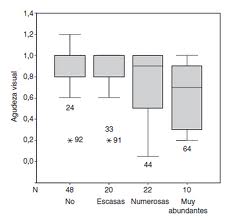

La pérdida del campo visual va desde 24% a 87% y por lo general progresa a un ritmo de alrededor del 1,6% al año.

En un análisis retrospectivo de 103 ojos completado por Grippo et al, las drusas visibles presentan pérdida de campo visual mucho máyor que aquellos con drusas enterradas.

La hipertensión ocular parece exacerbar la pérdida de campo visual con drusas del nervio óptico. En una serie de 103 ojos de 60 pacientes con drusas, la pérdida del campo visual estuvo presente en 20 de 22 (90,9%) ojos hipertensos, en comparación con 54 de 81 (66,7%) ojos normotensos.